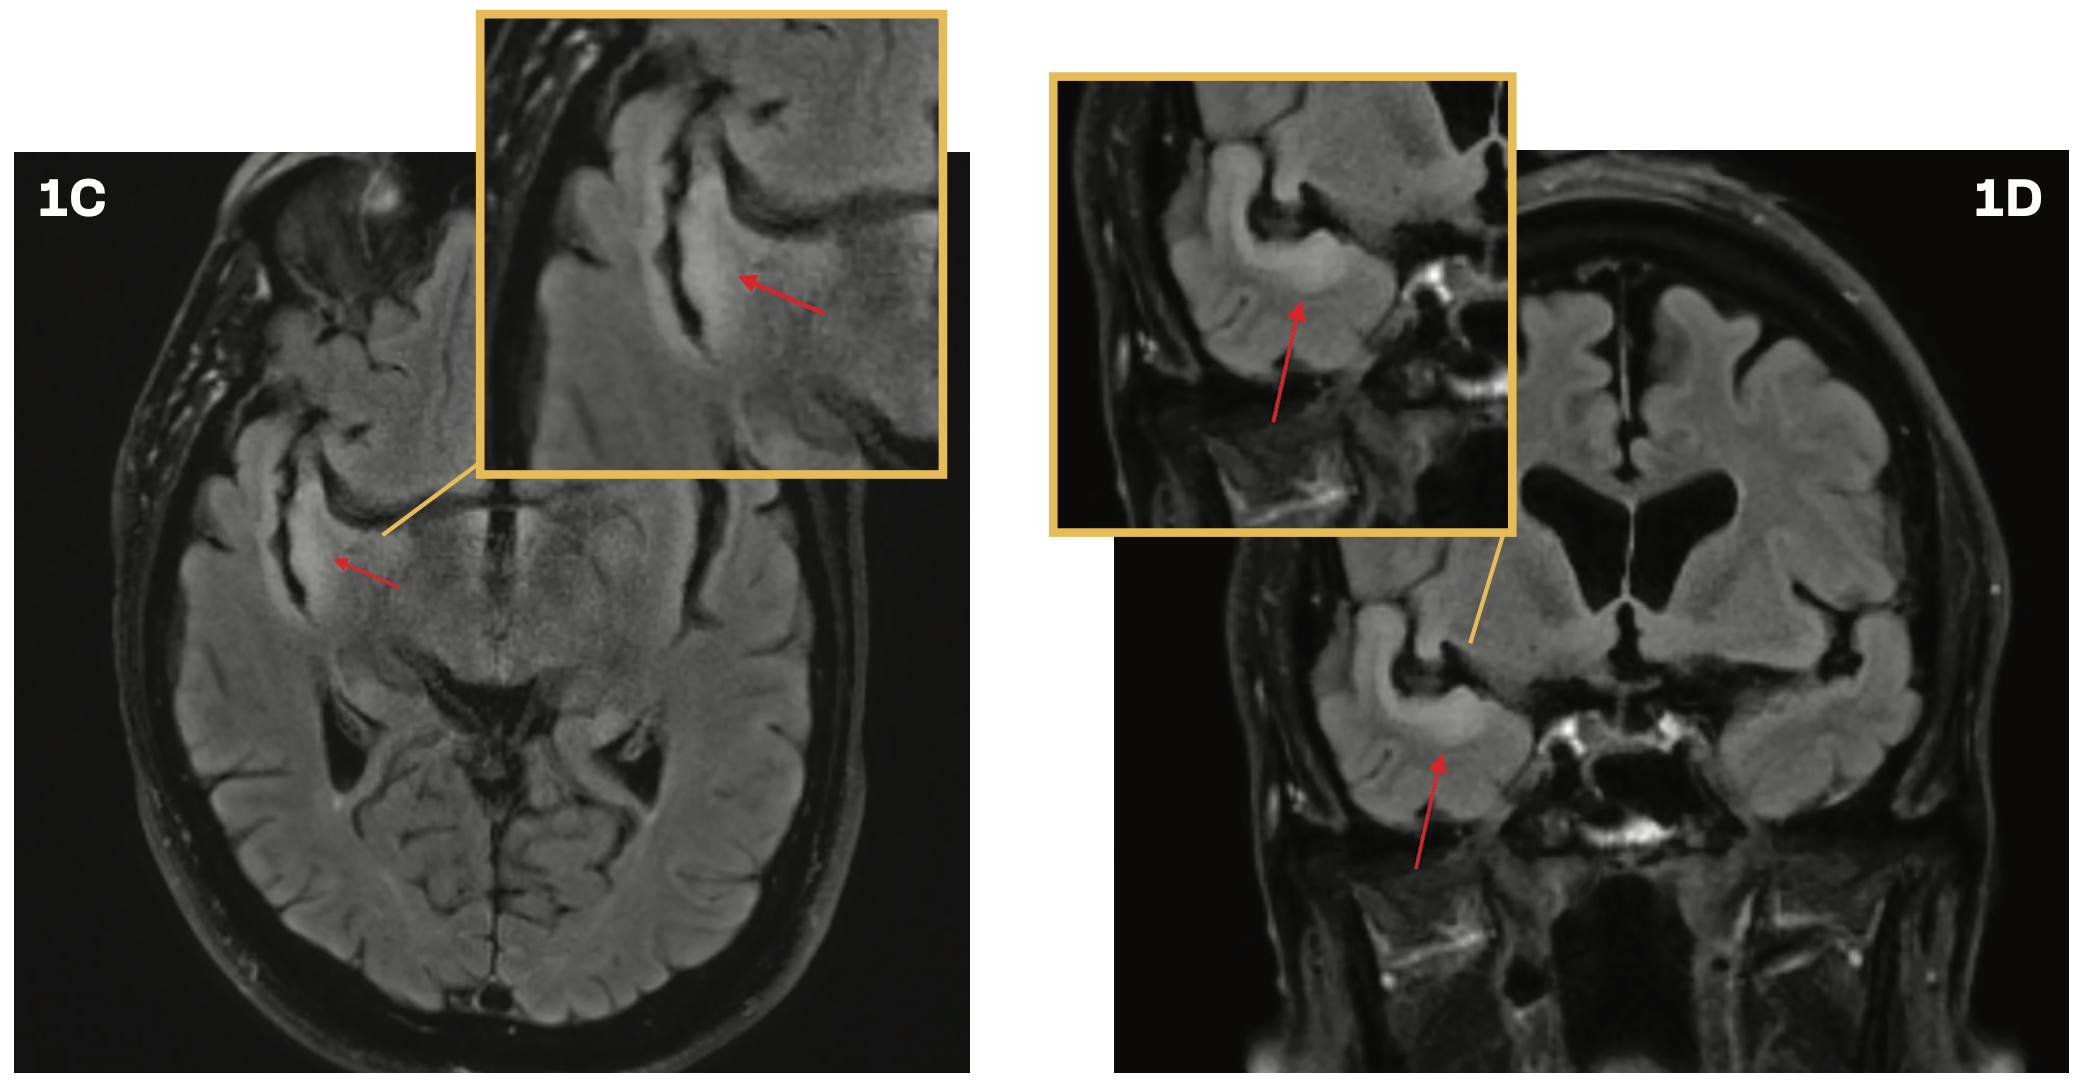

A 76-year-old man was evaluated in the emergency department following a mechanical fall that resulted in a head injury. He experienced a loss of consciousness for approximately 30 seconds. A CT scan of the head revealed no abnormalities. However, the patient continued to experience persistent headaches and dizziness. A brain MRI demonstrated subtle cortical thickening and a contiguous, non–mass-like increased T2 FLAIR signal along the temporal opercular and right insular cortex, without associated enhancement or restricted diffusion (Figures 1A and 1B), prompting a referral to neurosurgery for further evaluation. Subsequent brain MRIs performed 6, 12, and 22 months following the initial imaging did not show progression. However, at a 2.5-year

follow-up, brain imaging revealed progression of the T2 hyperintense abnormality along the ribbon of the superior temporal gyrus (Figures 1C and 1D). The radiographic findings suggested a potential low-grade glioma.

FIGURES 1A AND 1B. Brain MRI With Cortical Thickening

FIGURES 1C AND 1D. Brain Imaging at 2.5 Years’ Follow-Up